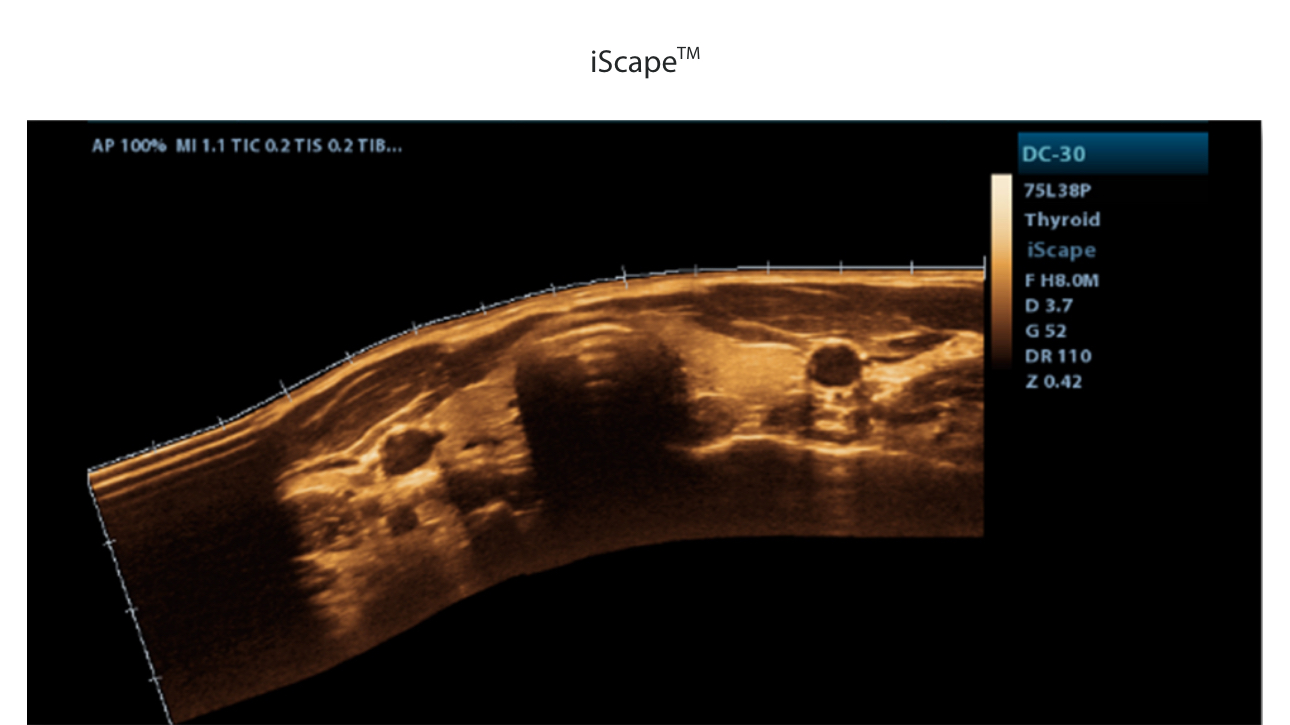

Standard ultrasound systems available today typically allow for a basic diagnosis but lack advanced functionality. Now, the DC-32 FullHD is the perfect answer for high-quality image performance, with 21.5 inches Full HD LED Monitor and advanced functions such as Auto IMT, iScape, Natural Touch Elastography, UWN Contrast Imaging and Tissue Doppler Imaging in General Imaging, and Smart OB, Smart face and iLive in OB.

Mindray DC 32 Full HD Ultrasound is a standard ultrasound system available today that typically allows for a basic diagnosis but lacks advanced functionality. Now, with the most competitive price in the industry, the DC-32 is the perfect answer for high-quality image performance, with added features such as Auto IMT, iScape, Natural Touch Elastography, UWN Contrast Imaging, and Tissue Doppler Imaging.

- iScape, Get a complete and extended view of the anatomical structure through panoramic imaging coupled with velocity indication and forward/backward scan ability making scanning much easier, smoother, and more controllable.